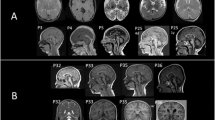

Lethal neonatal rigidity and multifocal seizure syndrome (RMFSL) is caused by variants in BRAT1 (BRCA1-associated protein required for ATM activation-1). However, the molecular mechanism of RMFSL is still unclear.

In this study, a novel homozygous BRAT1 variant c.233G > C with amino acid change of R with P at residue 78 (R78P) was identified. This variant altered the peptide structure and subcellular localization, as well as the expression in vitro. However, R78P did not alter the ability of BRAT1 to downregulate MitoSOX in mitochondria. Meanwhile, R78P BRAT1 was positively correlated with temporal lobe epilepsy, autosomal recessive primary microcephaly, defective/absent horizontal voluntary eye movements, and neuron apoptotic process as indicated by gene set enrichment analysis (GSEA).

The BRAT1 variant spectrum has been expanded, which will be helpful for genetic counseling. We also explored the molecular mechanism altered by R78P, which will provide a better understanding of the pathogenesis of RMFSL.

The detailed course of an infant with lethal neonatal RMFSL was depicted.

A novel disease-causing variant R78P in BRAT1 for lethal neonatal RMFSL was identified.